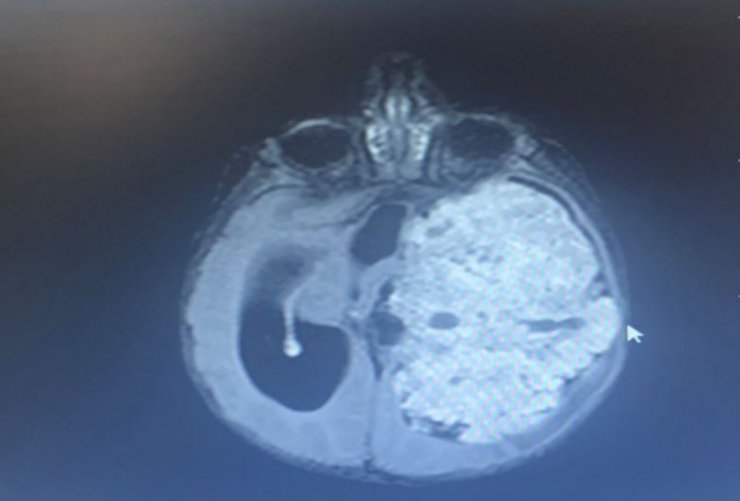

Şanlıurfa'da 1,5 yıllık evli Saniye ve Yunus Kılıç, 3 aylık bebekleri Mehmet Asaf Kılıç'ın kafasının sol tarafında oluşan şişliği fark edince Şanlıurfa Eğitim ve Araştırma Hastanesi'ne başvurdu. Beyninde kitle olduğu belirlenen Asaf bebek, Ankara Sağlık Bilimleri Üniversitesi Gülhane Eğitim ve Araştırma Hastanesi'ne sevk edildi. Asaf'ın çekilen MR'ında beynin sol tarafının tamamen tümör ile kaplı olduğu tespit edildi. Asaf bebeğin ameliyat edilmesi kararlaştırıldı ve 9 saat süren operasyonla beynindeki tümör temizlendi. Asaf bebek, tedavi sürecinin ardından sağlığına kavuştu.

Mehmet Asaf'ın doktoru Beyin ve Sinir Cerrahisi Uzmanı Doç. Dr. Cahit Kural, Asaf'ı ilk gördüklerinde yolunda gitmeyen bir şeyler olduğunu hissetiklerini belirterek, "Acil olarak MR çektirdik. Beyin MR'ında beynin sol tarafını tamamen dolduran, sağ tarafına bası yapan devasa bir kitle vardı. Zaman kaybetmeden hemen ameliyata aldık. Ameliyatta tümörün tamamını çıkardık. Bu büyüklükte tümörler çok nadir görülür. Beynin yarısını dolduran bir tümördü. Hastamız çok küçük, tümör çok büyük, riskli bir ameliyattı. 8-9 saat süren bir ameliyatın ardından iyileşti, sağlıklı şekilde evine gönderiyoruz" dedi.